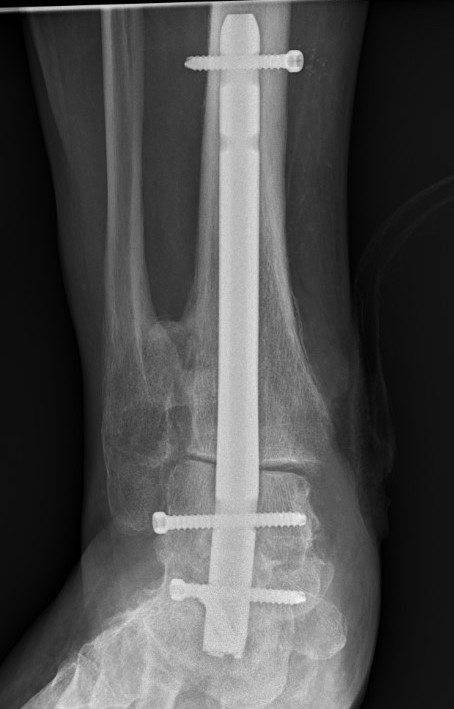

Tibiotalocalcaneal (TTC) / hindfoot nail

Insertion point

- in line with 2nd metatarsal / center of heel pad

- junction of posterior 2/3 and anterior 1/3 heel

- should pass through anterior aspect posterior subtalar joint

- posterior to lateral plantar artery and nerve

Screw fixation

- distal screw fixation in calcaneum +/- talus with jig

- compression

- proximal screws medial to lateral